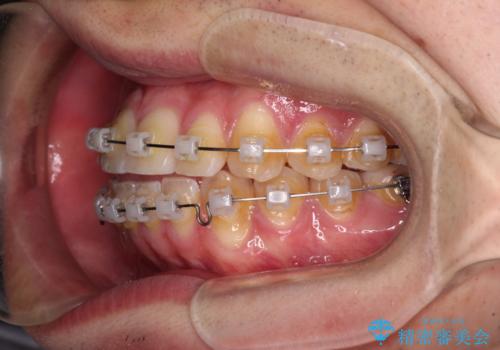

八重歯と前歯のクロスバイト ワイヤー装置で短期間矯正

- クリアブラケット

上顎側切歯(前から2番目の歯)が内側に転位している歯列は、インビザラインでは排列が困難であることが多いため、期間を短く、より良い仕上がりとするため、ワイヤー装置にて矯正治療を行うこととしました。

治療開始の頃は、食事や歯磨きが慣れず、装置が頻繁に脱落しましたが、2,3ヶ月ほどで慣れ、その後は1年ほどで治療を終えることができました。